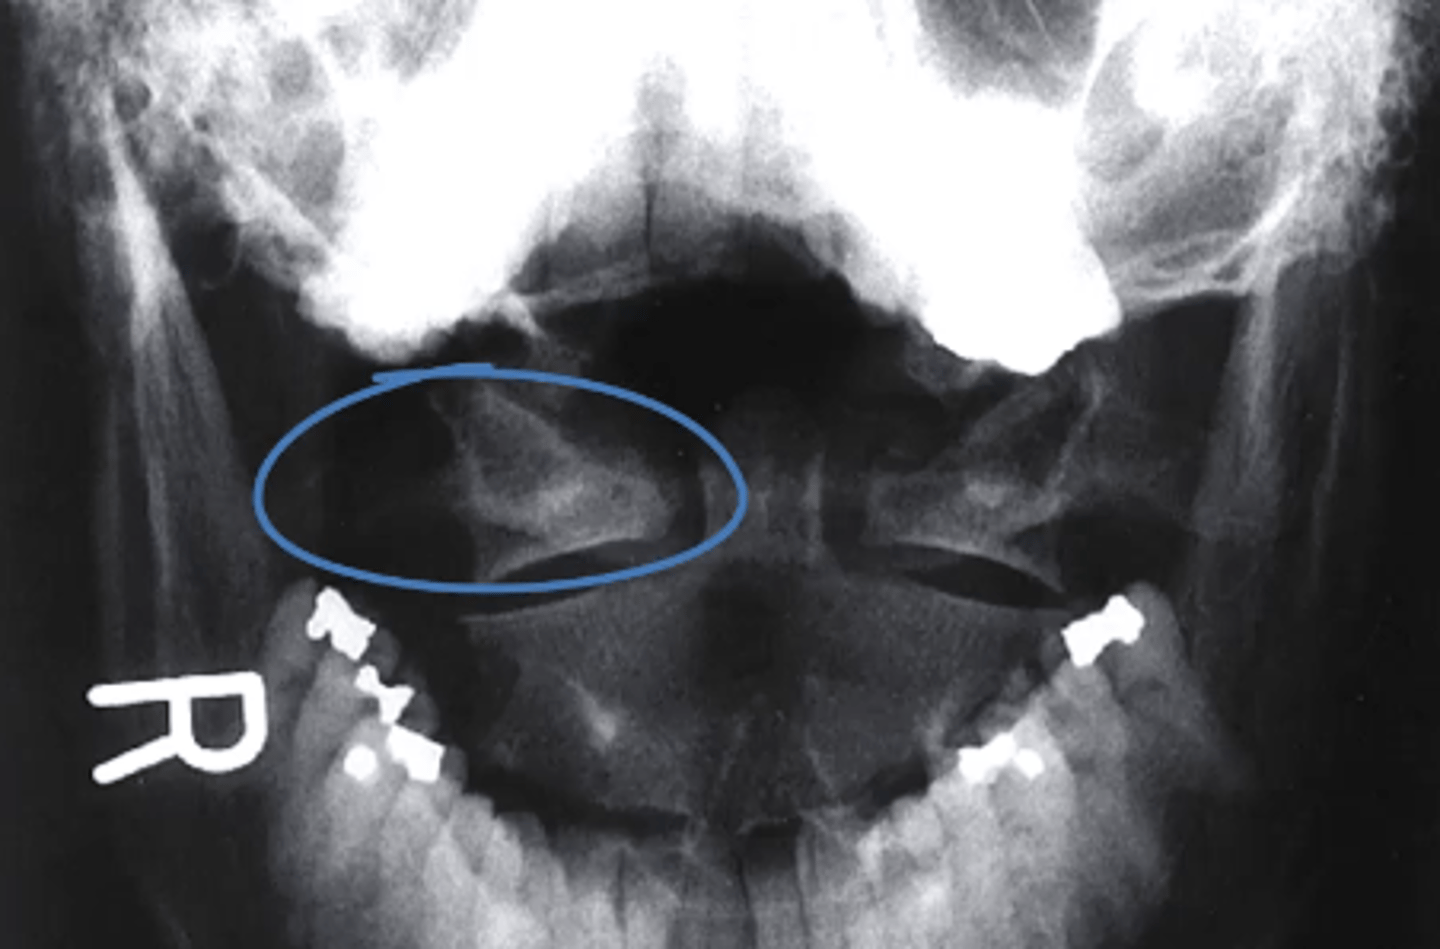

Lateral mass of the atlas

what structure is circled in blue?

a. Dens

b. Lateral mass of the atlas

c. Body of C2

d. condylar process

what can you see in an odontoid view?

-base of occiput

-angle of the mandible

-dens and body of C2

-anterior arch of the atlas

-posterior arch of the atlas

-lateral atlantoaxial facet joints

-bodies and spinous processes of C2-T1